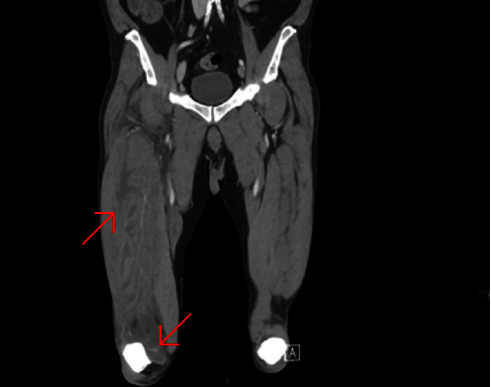

Pyomyositis, accompanied by aseptic arthritis, has been previously documented in several publications. However, none of the authors in the mentioned case reports offered a pathophysiological explanation for this unusual phenomenon or proposed a treatment protocol. We present a case of a healthy, 70-year-old male who was presented to the emergency department 4 days after tripping over a pile of wooden planks and getting stabbed by a nail to his thigh. The right thigh was swollen. Unproportional pain was produced by a light touch to the thigh. A laboratory test and a CT scan were obtained. The working diagnosis was pyomyositis of the thigh and septic arthritis of the ipsilateral knee. The patient underwent urgent debridement and irrigation of his right thigh. An arthroscopic knee lavage was performed as well. Intraoperative cultures from the thigh revealed the growth of Streptococcus pyogenes and Staphylococcus aureus. Cultures from synovial fluid were sterile; thus, septic arthritis was very unlikely. The source of the knee effusion might have been an aseptic inflammatory response due to the proximity of the thigh infection. Anatomically, the quadriceps muscle inserts on the patella, and its tendon fuses with the knee capsule, creating a direct fascial track from the thigh to the knee. The inflammatory response surrounding the infection may have followed this track, creating a domino effect, affecting adjacent capillaries within the joint capsule, and causing plasma leakage into the synovial space, leading to joint effusion. Our suggested treatment is addressing the primary infection with antibiotics and considering adding anti-inflammatory therapy, given our suspicion that this process has an inflammatory component.

Abstract Image